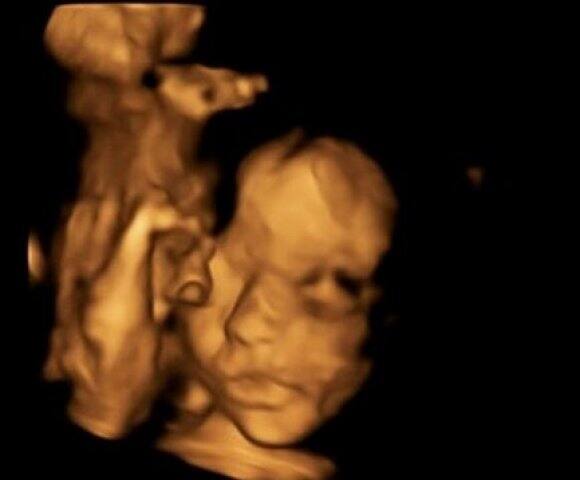

অবিশ্বাস্য! গর্ভস্থ শিশুকে মায়ের জঠর থেকে বের করে সফল অস্ত্রোপচারের পর ফের গর্ভে ঢুকিয়ে দিলেন চিকিৎসকরা

সিম্পসন জানান, এই অস্ত্রোপচারের সময় তাঁর পাশে বিশ্বের তামাম শ্রেষ্ঠ চিকিৎসকরা উপস্থিত ছিলেন। তাঁরা সকলে মিলে ওই অস্ত্রোপচার সফল করেন। প্রসঙ্গত, ইংল্যান্ডে এই প্রথম এমন সার্জারি সফলভাবে করলেন চিকিৎসকরা।

চিকিৎসকরা প্রথমে সিম্পসনকে গর্ভপাতের পরামর্শ দেন। কিন্তু, সিম্পসন রাজি হননি। তখন চিকিৎসকরা ফিটাল সার্জারির পরামর্শ দেন। যা মেনে নেন সিম্পসন ও তাঁর স্বামী।